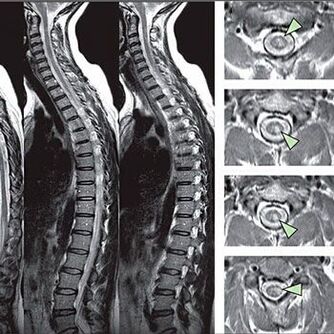

Tundlikkuse häirete tunnuste tuvastamiseks viiakse läbi spetsiaalsed funktsionaalsed testid. Instrumentaalsete meetodite diagnoosimise kõige informatiivsem võimalus on X -RAY jõudlus. Lülisamba põhjalikuks uurimiseks viiakse MRI ja CT sageli läbi. Kardiovaskulaarsüsteemi haiguste kahtluse korral soovitatakse patsiendil läbida EKG protseduur.